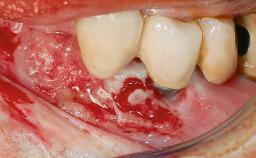

Excess Cement Resulting in Peri-implant Infection Presenting as a Draining Sinus Tract

Biological complications caused by undetected cement residue have been receiving much attention. Excess cement might be responsible not only for rapidly developing of peri-implantitis, but also for delayed or chronic manifestations of the disease many years after cementation (Wilson 2009; Linkevicius and coworkers 2013). Invitro and clinical studies have shown that it is very difficult or even impossible to completely clean up excess cement at subgingival margins, so popular in cemented restorations (Agar and coworkers 1997; Linkevicius and coworkers 2011, 2012). Possible outcomes of biological complications due to excess cement range from temporary inflammation of the peri-implant soft tissues without any serious esthetic and functional consequences all the way to implant loss. This report describes a case of peri-implantitis caused by residual cement; as well as the management and quite unusual resolution of the complication. The patient presented in 2009 with a draining sinus tract, tenderness on chewing, and tissue contact above the implant-supported restoration. The implant had been restored approximately three years before.